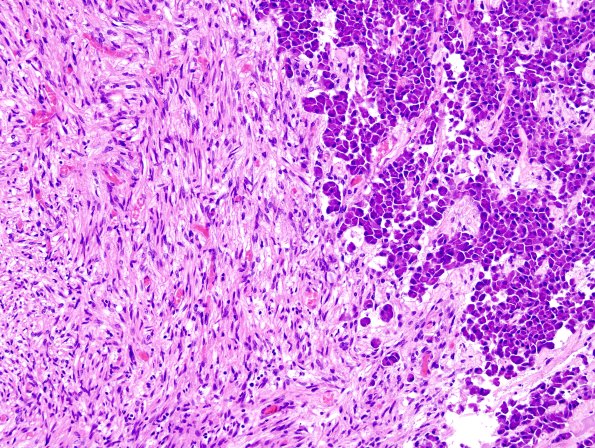

6C3 Pituitary, normal basophil invasion H&E 5

Increasing magnification of basophil invasion. (H&E)